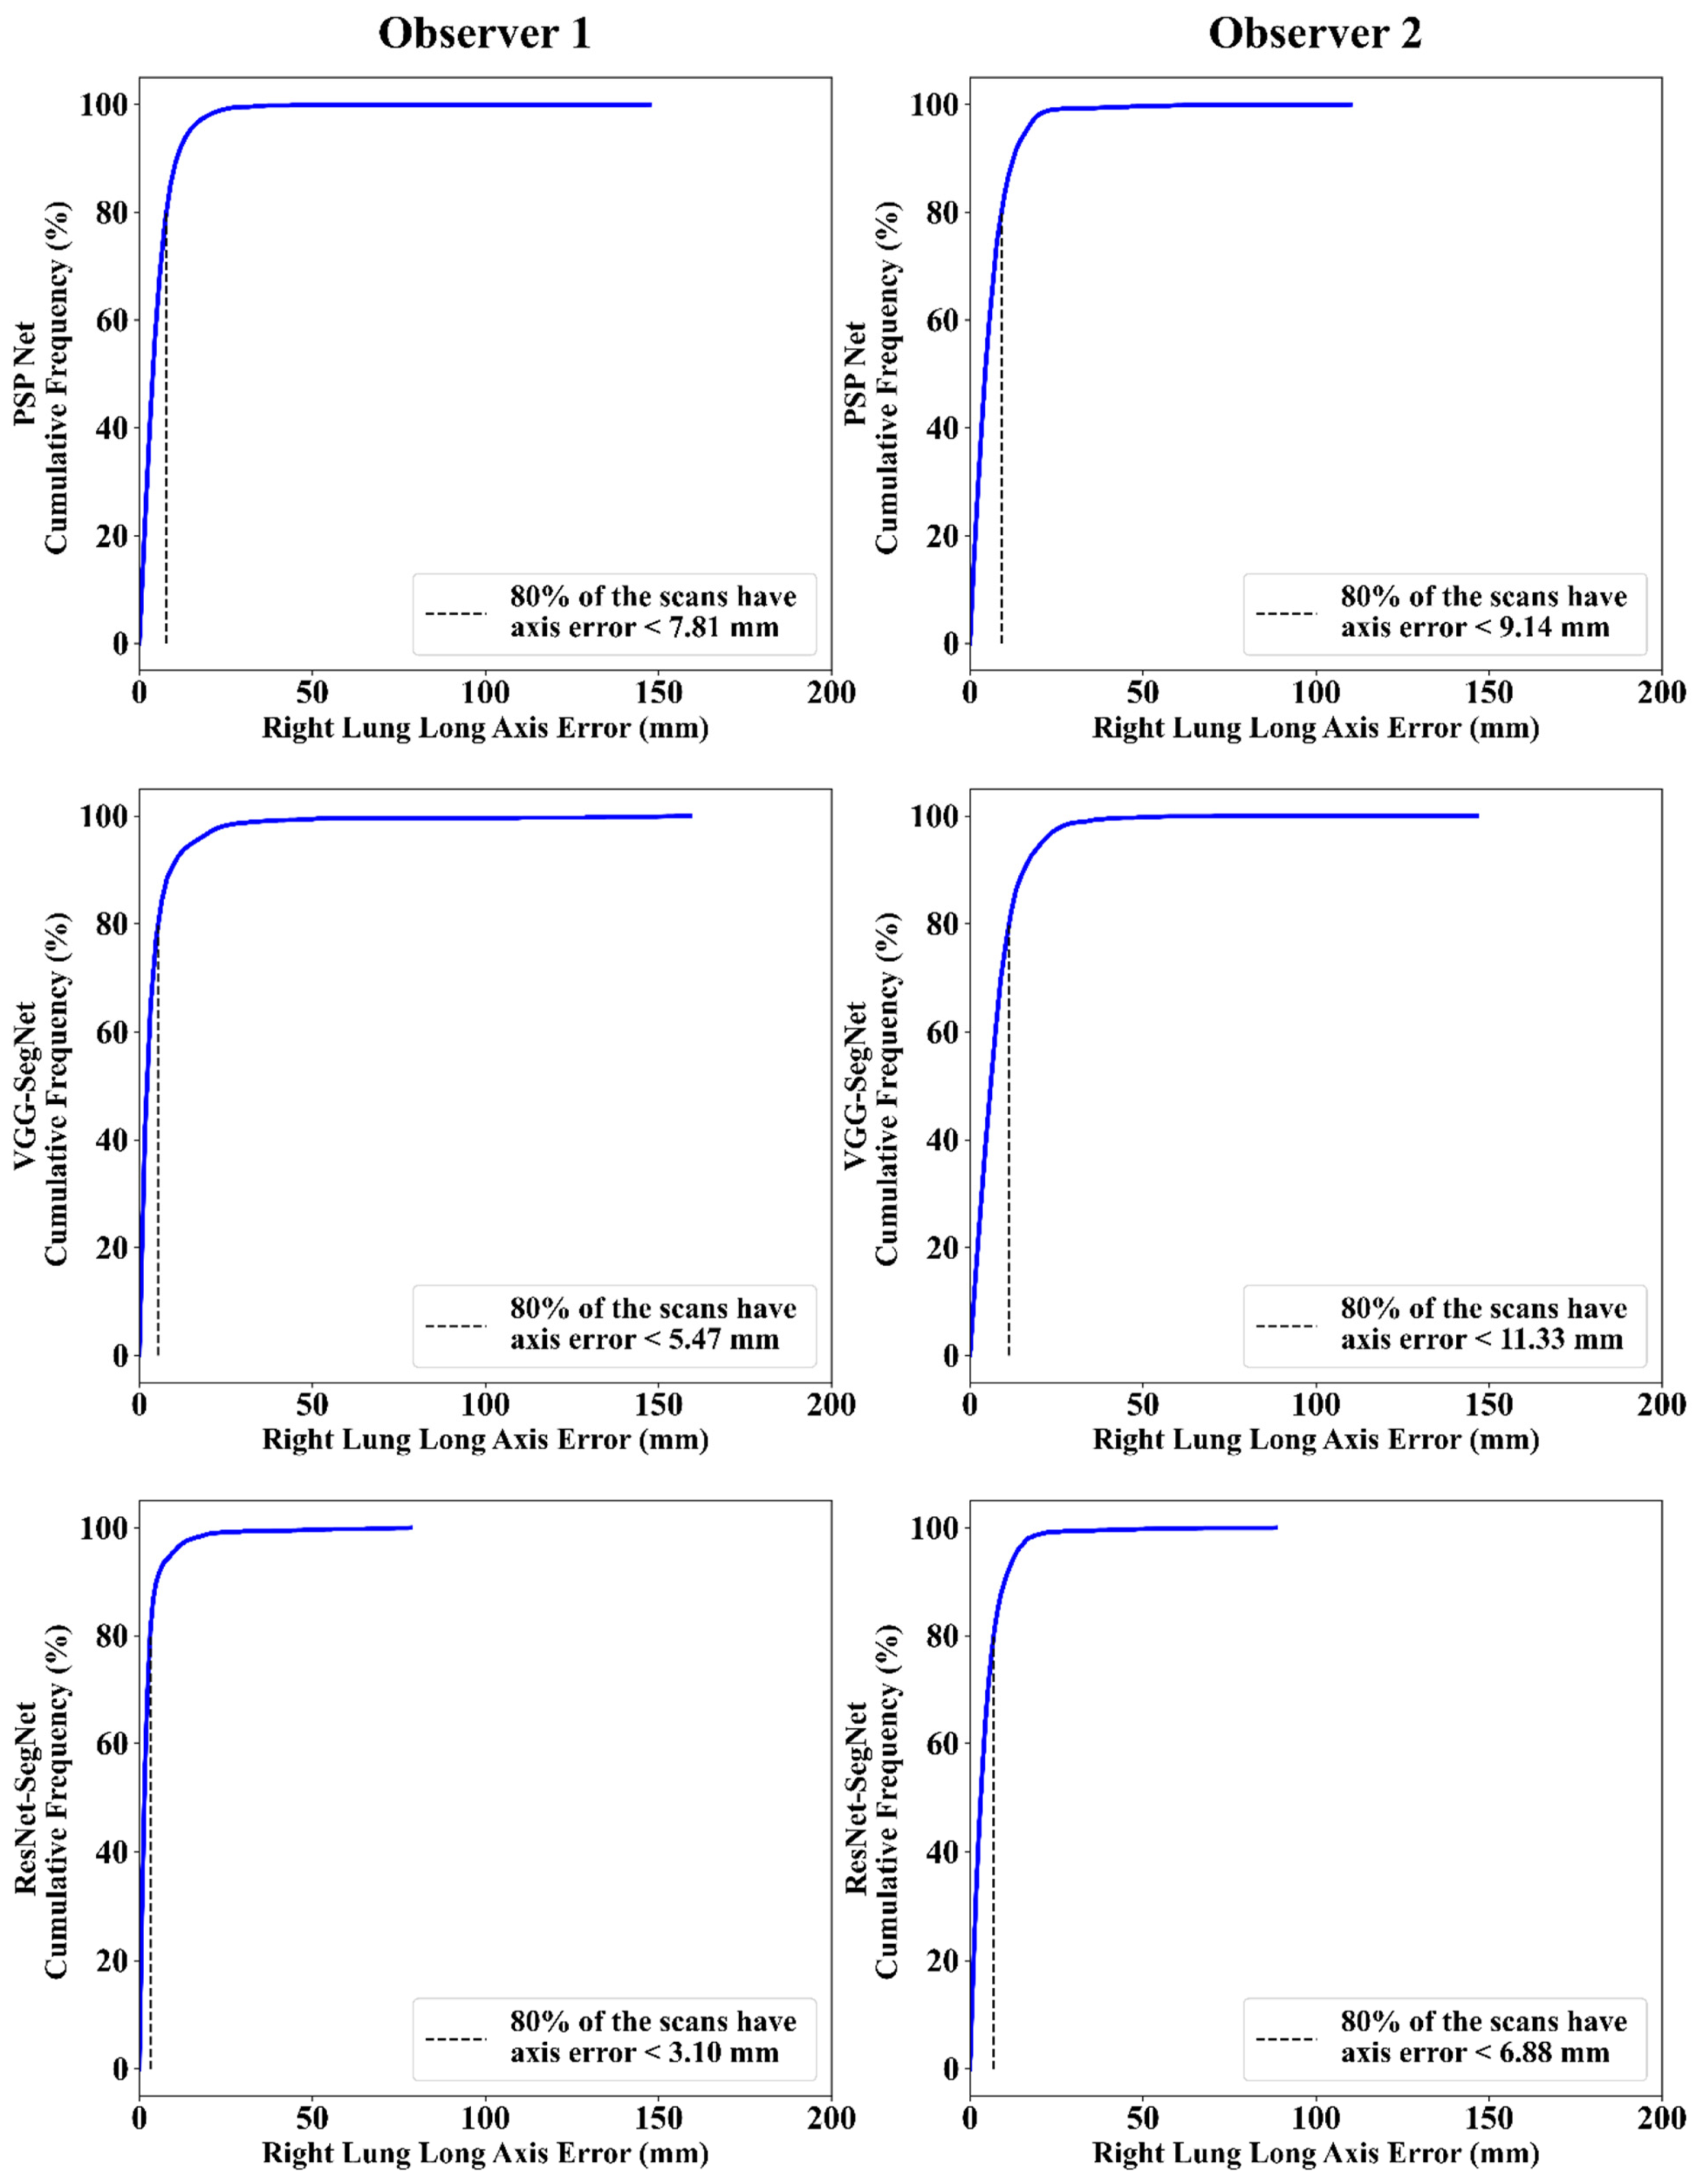

Cumulative Frequency Plot for Lung Long Axis Error

Correlation Plot for Lung Long Axis Error